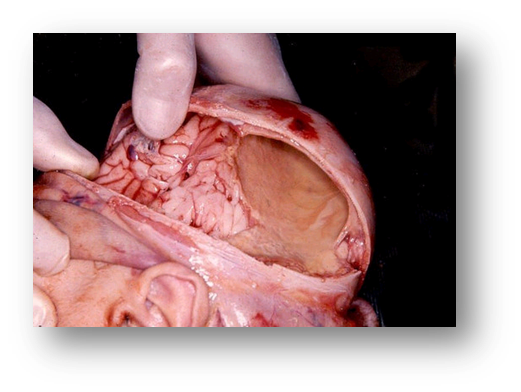

2. El daño cerebral adquirido se considera a cualquier tipo de lesión o cambios que sufre el cerebro por el que surgen alteraciones en el funcionamiento normal, bien por un traumatismo craneal, una isquemia (también conocida por ictus, accidente cerebro-vascular, infarto cerebral), tumores cerebrales, hidrocefalias, anoxias,

1. DAÑO CEREBRAL

1. Adquirido:

1. daño al tejido vivo del cerebro que inicialmente es causado por fuerzas mecánicas externas

2. No Adquirido

1. Tumores

1. ECV o ACV

1. TCE Traumas craneoencefalicos

1. Abiertos

1. Cerrados